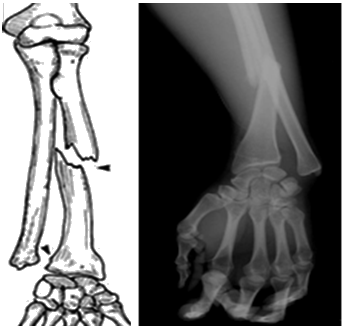

盖氏(Galeazzi)骨折桡骨干下1/3骨折合并尺骨小头脱位

盖氏(Galeazzi)骨折